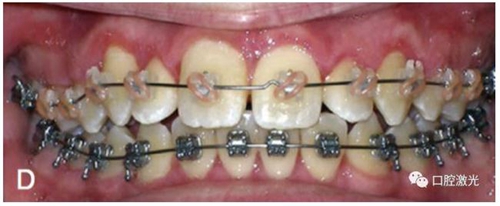

有時,會遇到一些口腔衛(wèi)生問題比較嚴重的患者,從而導致牙齦發(fā)炎而腫大。通過改善口腔衛(wèi)生環(huán)境,炎癥可以得到緩解,但增生的牙齦不一定都可以完全恢復。下圖的患者就存在口腔牙齦肥厚問題,同時左上部犬牙存在部分萌出的問題,右上部犬牙存在未萌出問題,這些問題都妨礙了托槽的粘接。因此,實施了全口腔的牙齦整形手術(shù)。去除了多余的牙齦組織,增加了犬牙的暴露面積,從而使托槽的粘接更為便利,同時也提升了患者保持口腔衛(wèi)生的狀況。

激光治療當天粘接托槽

6周后效果